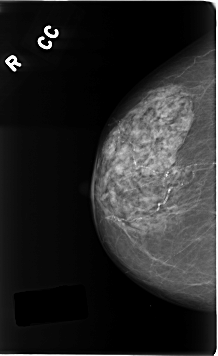

C_0196_1.RIGHT_CC

RIGHT_CC LINES 4616 PIXELS_PER_LINE 2824 BITS_PER_PIXEL 12 RESOLUTION 50 NON_OVERLAY